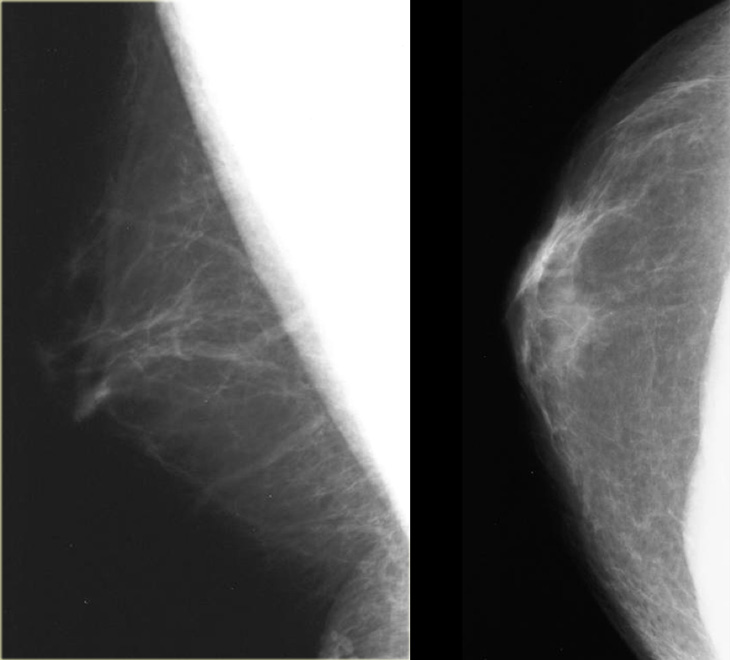

( A ) Синдром Поланда с отсутствием грудных мышц и недостаточностью мягких тканей в подключичной области, хорошо развитой грудью (обратите внимание на боковую и верхнюю проекции груди из-за отсутствия нижележащей грудной мышцы) (Перепечатано с разрешения Caouette-Laberge L. , Бортолуцци П.Коррекция асимметрии груди у подростков. В: Холл Финдли Э., Эванс GRD, ред. Эстетическая и реконструктивная хирургия груди. Филадельфия, Пенсильвания: Saunders Elsevier; 2010: 601–629). ( B ) Трансплантация мышечно-кожной широчайшей мышцы с введением деэпителизированного островка кожи в подключичной области. ( C ) Послеоперационный период в покое (перепечатано с разрешения Caouette-Laberge L, Bortoluzzi P. Коррекция асимметрии груди у подростков. В: Hall Findley E, Evans GRD, eds. Эстетическая и реконструктивная хирургия груди.Филадельфия, Пенсильвания: Saunders Elsevier; 2010: 601–629). ( D ) Послеоперационный снимок с мышечным сокращением, показывающий скрытую мягкую ткань в подключичной области (перепечатано с разрешения Caouette-Laberge L, Bortoluzzi P. Коррекция асимметрии груди у подростков. В: Hall Findley E, Evans GRD, eds. Aesthetic and Реконструктивная хирургия груди, Филадельфия, Пенсильвания: Saunders Elsevier, 2010: 601–629).

, Бортолуцци П.Коррекция асимметрии груди у подростков. В: Холл Финдли Э., Эванс GRD, ред. Эстетическая и реконструктивная хирургия груди. Филадельфия, Пенсильвания: Saunders Elsevier; 2010: 601–629). ( B ) Трансплантация мышечно-кожной широчайшей мышцы с введением деэпителизированного островка кожи в подключичной области. ( C ) Послеоперационный период в покое (перепечатано с разрешения Caouette-Laberge L, Bortoluzzi P. Коррекция асимметрии груди у подростков. В: Hall Findley E, Evans GRD, eds. Эстетическая и реконструктивная хирургия груди.Филадельфия, Пенсильвания: Saunders Elsevier; 2010: 601–629). ( D ) Послеоперационный снимок с мышечным сокращением, показывающий скрытую мягкую ткань в подключичной области (перепечатано с разрешения Caouette-Laberge L, Bortoluzzi P. Коррекция асимметрии груди у подростков. В: Hall Findley E, Evans GRD, eds. Aesthetic and Реконструктивная хирургия груди, Филадельфия, Пенсильвания: Saunders Elsevier, 2010: 601–629).